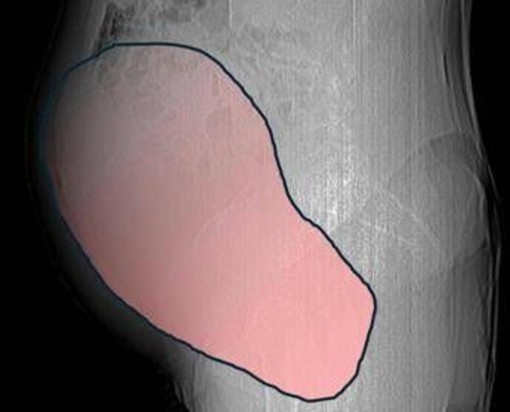

(Adnkronos) - Una donna di 69 anni ha scoperto di essere affetta da un tumore ovarico di dimensioni eccezionali, paragonabili a quelle di una gravidanza gemellare a termine, solo quando il suo organismo ha improvvisamente iniziato a cedere. Per mesi la gigantesca cisti ovarica, con un diametro di circa 28 centimetri, è rimasta nascosta, senza dare segnali evidenti. La paziente non si era accorta di nulla. L’allarme è scattato quando la massa, associata alla presenza di una seconda neoplasia intestinale, ha iniziato a comprimere il colon, provocando sintomi acuti ed improvvisi fino ad una grave difficoltà intestinale non più ignorabile. A riferire la storia è l'ospedale Sant'Anna di Torino.

Il caso risale a metà dicembre quando la donna arriva all’attenzione dei sanitari e a prendere in carico il caso è la Chirurgia Ginecologica Mininvasiva dell'ospedale Sant’Anna diretta dal dottor Paolo Petruzzelli. I tempi sono strettissimi, con le festività natalizie alle porte, ma la risposta è immediata: in pochi giorni si definisce l'inquadramento diagnostico, stadiazione e percorso terapeutico. Il 23 dicembre, a poche ore dalla vigilia di Natale, la paziente entra in sala operatoria. L’intervento dura circa sei ore. ''Durante l’intervento emerge tutta la gravità della situazione - spiegano dall'ospedale - La gigantesca neoplasia ovarica viene asportata: pesa circa 6 chilogrammi, con un volume paragonabile a quello di una gravidanza gemellare a termine. Ma non è l’unica minaccia. I sintomi più pericolosi sono legati alla sofferenza intestinale, che richiede un intervento immediato e coordinato di più specialisti''.